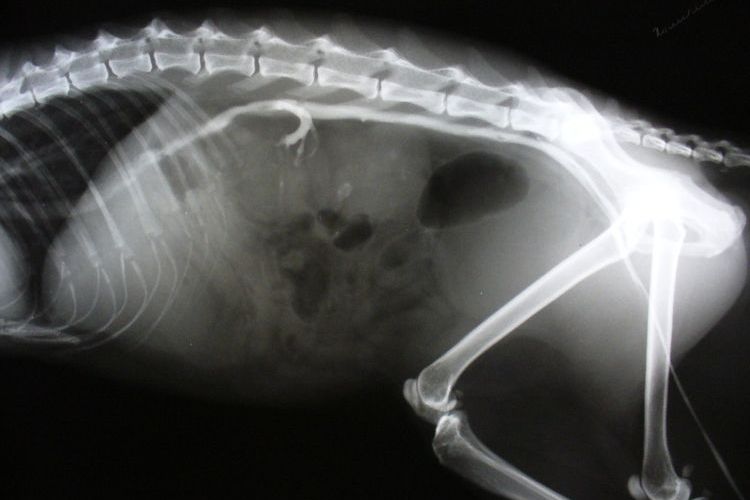

Des symptômes évidents et douloureux indiquent généralement l'apparition d'une insuffisance rénale. Par conséquent, le vétérinaire effectuera probablement des examens diagnostiques, en se concentrant sur le système urinaire. Une numération formule sanguine complète, incluant un bilan biochimique, est réalisée en premier lieu. Les reins filtrant les toxines du sang (qui sont ensuite éliminées dans l'urine), une analyse d'urine complète constitue également un outil diagnostique efficace. Une fois le diagnostic préliminaire confirmé, le vétérinaire prescrira des radiographies et une échographie. Les radiographies permettront une évaluation précise de la taille et de la localisation des kystes.

Ultrason — une méthode précise et relativement peu coûteuse pour diagnostiquer le syndrome des ovaires polykystiques, adaptée à l'examen des animaux adultes. Chez les chatons de moins de neuf mois, les kystes peuvent ne pas être visibles.